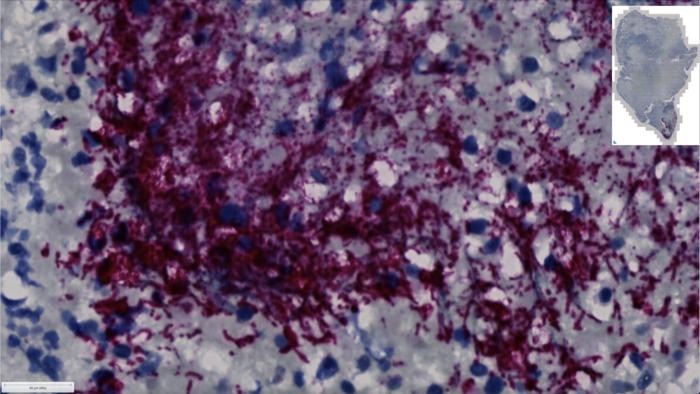

當(dāng)研究人員發(fā)現(xiàn)口腔中一種特定亞型的細(xì)菌能夠在結(jié)直腸癌(CRC)腫瘤內(nèi)生長時,這給結(jié)直腸癌的治療方法和早期篩查帶來了重要的啟示。美國癌癥學(xué)會稱,結(jié)直腸癌是美國成年人第二大癌癥死因。弗雷德·哈欽森癌癥中心的研究人員發(fā)現(xiàn),一種名為Fusobacterium nucleatum animalis(Fna)亞種的特定亞型,即Fna C2,在結(jié)直腸癌腫瘤內(nèi)生長,驅(qū)動著癌癥的進(jìn)展,并導(dǎo)致癌癥治療后患者預(yù)后較差。

在這項最新研究中,研究人員發(fā)現(xiàn),結(jié)直腸癌腫瘤中的主要一組Fusobacterium nucleatum,原以為是單一的亞種,實際上由兩個不同的譜系組成,即Fna C1和Fna C2。通過分析這些譜系之間的遺傳差異,研究人員發(fā)現(xiàn),腫瘤浸潤的Fna C2型已經(jīng)獲得了與其能夠從口腔通過胃到達(dá)下消化道、經(jīng)受胃酸并在下消化道生長相關(guān)的獨特遺傳特征。

進(jìn)一步的分子分析顯示,在200多例結(jié)直腸癌腫瘤中,F(xiàn)na C2譜系在約50%的病例中存在。在成百上千例結(jié)直腸癌患者和健康人的大便樣本中,研究人員發(fā)現(xiàn)Fna C2水平在結(jié)直腸癌中持續(xù)較高?!芭c我們在CRC腫瘤組織中的觀察類似,我們的數(shù)據(jù)表明,在CRC患者的大便中,F(xiàn)na C2更普遍且更豐富,而且與健康個體相比,F(xiàn)na C2是唯一在CRC患者的大便中明顯富集的Fn亞組?!毖芯咳藛T還在一種結(jié)直腸癌的小鼠模型中發(fā)現(xiàn),使用Fna C2治療的動物出現(xiàn)了更多的腸腺瘤和代謝產(chǎn)物的改變。